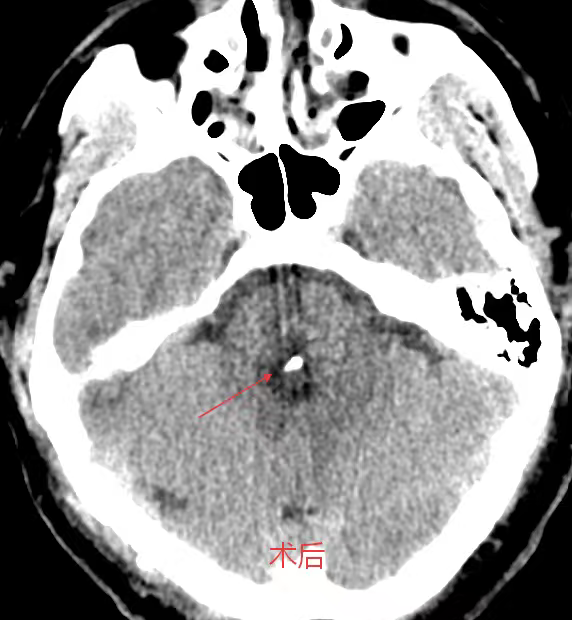

考虑到患者年轻、基础状况尚可,且出血部位深、传统开颅手术创伤大、风险高,医生团队决定采用脑立体定向仪引导下的微创穿刺血肿碎吸术。

主刀医生龙青山介绍,“我们利用立体定向系统,将穿刺误差控制在2毫米以内,仅需一个约3厘米的小切口,通过直径不足1厘米的骨孔置入穿刺管,直接进入血肿腔。”

手术过程历时一个多小时

共抽出近8毫升血块

术后复查显示

血肿清除率接近100%

术后